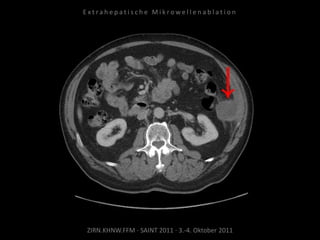

Bildgebung vor MWA:

CT 09.09.2010

Situation:

Tumorerkrankung mit ausgedehnter

Metastasierung. Schmerzsymptomatik

durch Metastasen am Truncus coeliacus.

Ziel:

Druckreduzierung durch Reduzierung

der Tumorlast, thermische Reduktion

der Schmerzfasern am Truncus, dadurch

Reduzierung der hierdurch bedingten

Beschwerden. Kein kurativer Ansatz.

Indikation zur MWA:

Aufgrund der gefäßnahen Lage stellt die

MWA mit ihrer der exakten

Positionierbarkeit und dem exakt

definierten Ablationsvolumen die

Methode der Wahl dar.

Ablation am 07.10.2010:

Je eine Nadelposition von links und

von rechts.